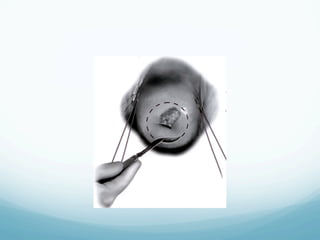

Sharp Conization

—  One of the oldest techniques

—  Recommended for women with suspected

microinvasion and AIS

—  The margins of the cone are plotted colposcopically

using acetic acid or Lugol s solution

—  The configuration of the specimen is based on the

extent of disease

—  Complications include: bleeding (immediate or

delayed), cervical stenosis, cervical incompetence

Sharp Conization —  Oneof the oldest techniques —  Recommended for women with suspected microinvasion and AIS —  The margins of the cone are plotted colposcopically using acetic acid or Lugol s solution —  The configuration of the specimen is based on the extent of disease —  Complications include: bleeding (immediate or delayed), cervical stenosis, cervical incompetence